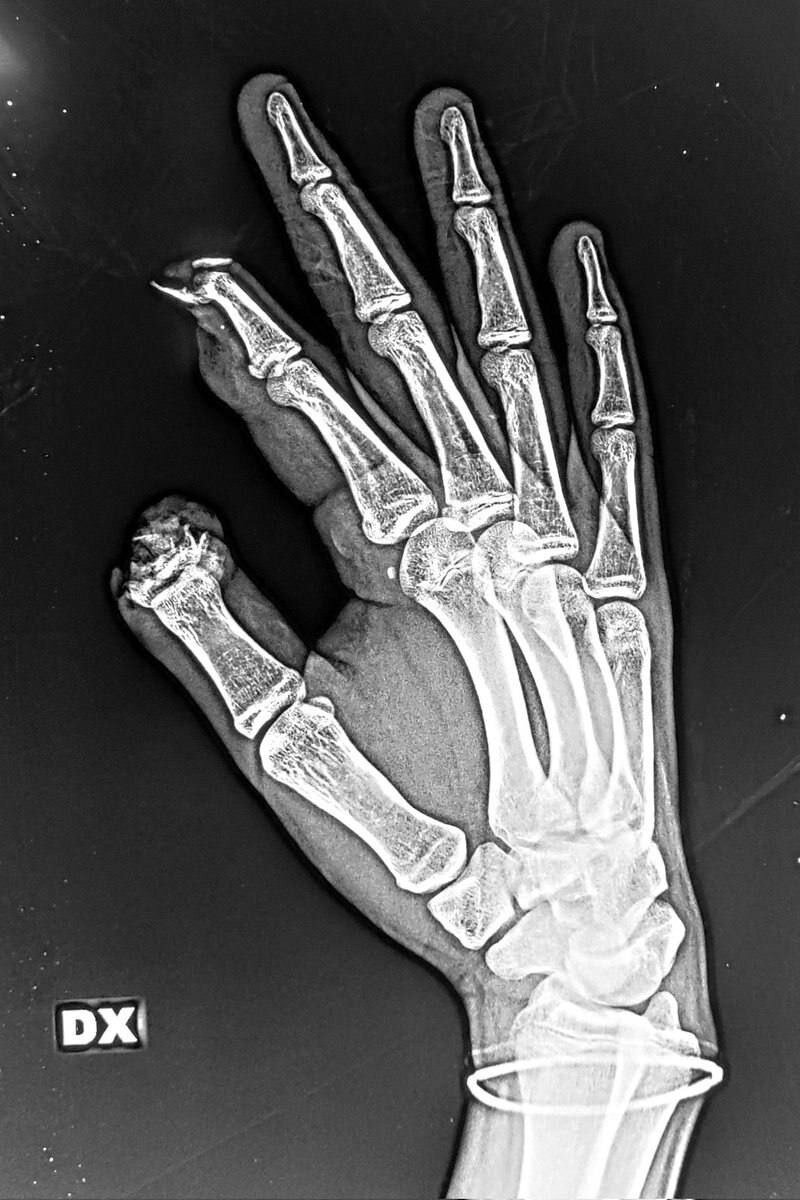

Как итог - минус две фаланги на правой руке. Напоминаем о правилах обращения с пиротехникой. Берегите себя! Больше напоминаний о безопасности в нашем ТГ канале:

В новогоднюю ночь у 15-летнего зумера в руках взорвалась петарда.